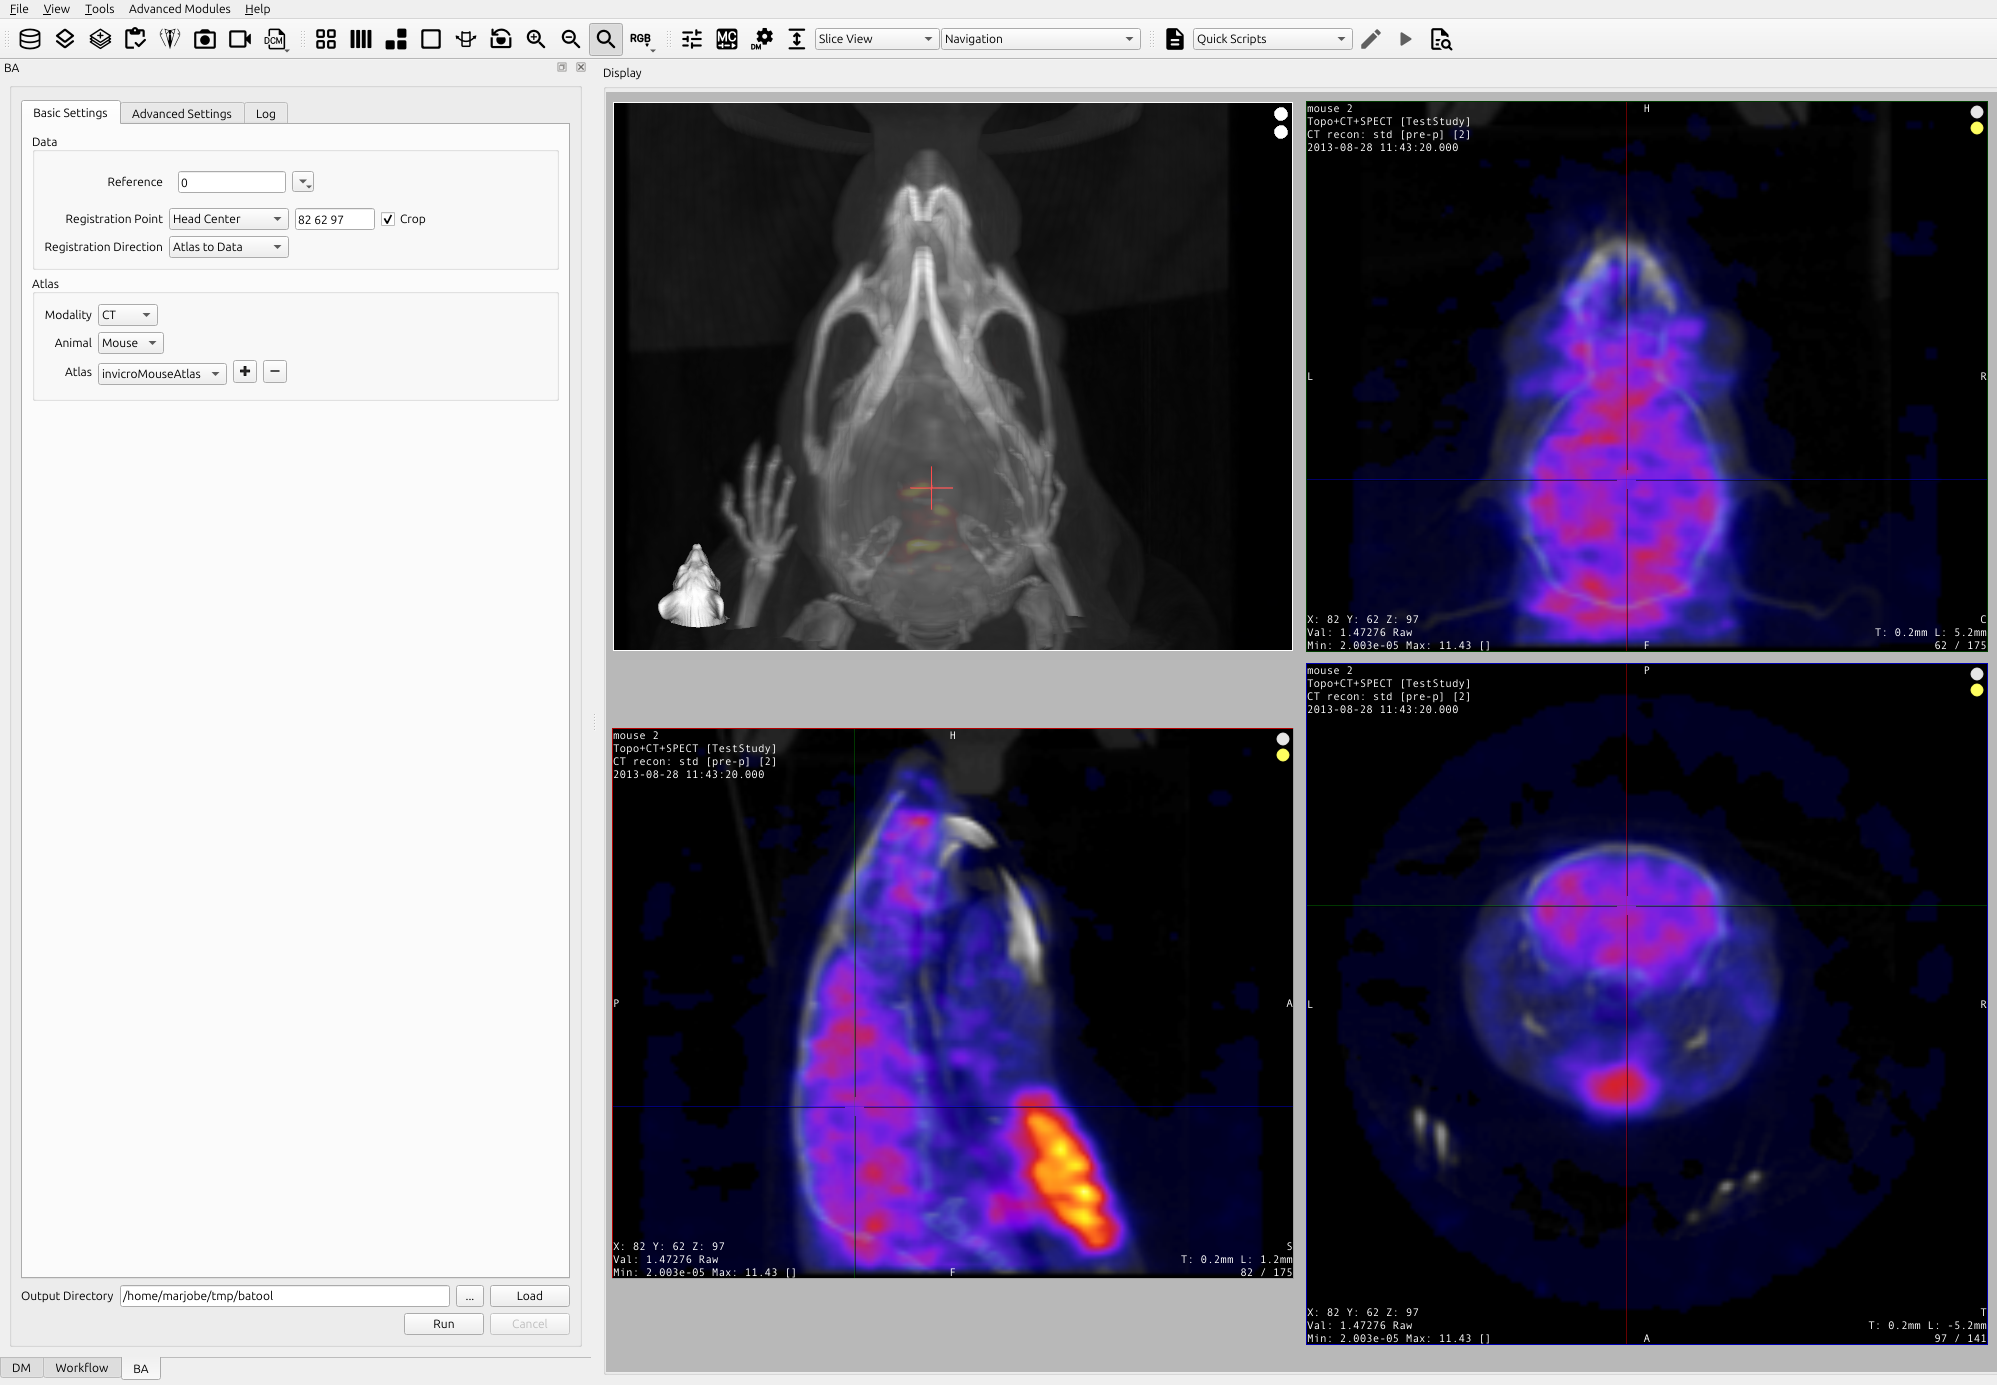

Providing a seed point is necessary if the images are not focused around the head/brain. To provide a seed point please place the cursor in the center of the brain in the Sagittal, Coronal, and Transverse views as seen in the image below.

3D Brain Atlas Tool Settings GUI: Basic Settings

Getting There

To open the Atlas Tool settings GUI, please go to Advanced Modules > 3D Brain Atlas Tool

Basic Settings Tab

Data

Reference

Choose the reference image to perform the brain atlas

Registration Point

Select the registration point.

- Choose “Head Center”: will center the reference’s head and do all the operations to present the brain atlas, it is the best method for cropped output. Options ‘Registration Direction’ and ‘Crop’ are enabled for this technique.

- Choose “Cursor Seed Point”: will seed the operation with the crosshair point in order to present the brain atlas, it is the best method for non-cropped output. In this technique ‘Registration Direction’ is “Atlas to Data” and ‘Crop’ is unchecked, both always fixed.

Registration Direction

Select the registration direction.

- Choose “Data to atlas” to transform the image data (including anisotropic scaling and shearing) to match the atlas.

- Choose “Atlas to data” to transform the atlas to match the anatomical reference image.

Crop

Check the crop box if the data are not focused. The current head center (or seed point) will be displayed. To update the head center with the tool window open, use the mouse scroll wheel to move the crosshairs.

Atlas

Modality

Select the modality of the anatomical reference image. We currently support CT and MR images. If the image is tagged with modality information, the tool should detect this automatically.

Animal

Select the appropriate animal type.

- For CT registration, we currently support mouse, rat, squirrel monkey, and cynomolgus monkey.

- For MR registration, we currently support mouse, rat, canine, cynomolgus monkey, and rhesus monkey.

Select the appropriate atlas type. These are populated based on the modality, animal type, and contents of the user’s atlas directory.

Output Directory

Select the output directory in which to store results. If there are existing results in this directory, they will be deleted when the tool is run. To load the existing results click the Load button. The following will be stored here:

Run the Tool

Click the Run button to begin processing. The dialog window will switch to the “Log” tab where progress updates are displayed.

- Click the Cancel button to attempt to abort processing. This will stop processing after the current stage of processing has finished. As registration accounts for most of the processing time, this may not be responsive.

- When the tool finishes, results will load automatically (including the CSV file) and VQ will finish in the 3D ROI tool.

- Processing time will depend upon the computer’s inherent capabilities and the file size of the image files.